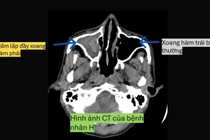

Nếu bị viêm xoang do nấm mà không điều trị kịp thời có thể gây nhiều biến chứng nặng như phá hủy các thành xoang, xâm lấn hốc mắt, sọ não gây mù lòa, viêm màng não, thậm chí ảnh hưởng đến tính mạng.